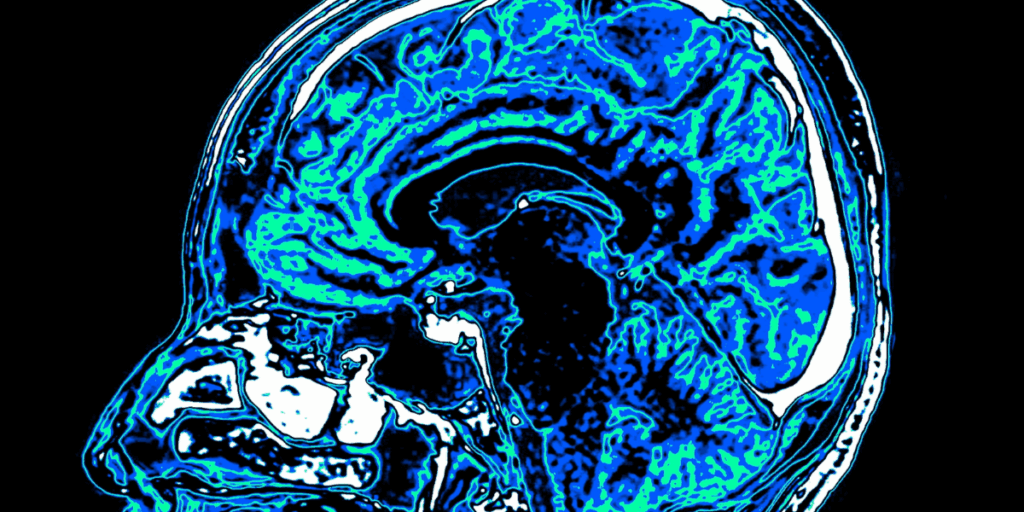

Neuropsykolog i opråb: Trumps bizzare opførsel afslører mulig sygdom

Neuropsykolog Dr. Narinder Kapur peger på præsidentens bizarre udtalelser og fejl som tegn på mulig kognitiv svækkelse.

Neuropsykolog Dr. Narinder Kapur mener, at Donald Trump bør gennemgå en Alzheimers-test. Han peger på flere episoder med mærkelig opførsel, som ifølge ham kan tyde på begyndende kognitiv svækkelse.